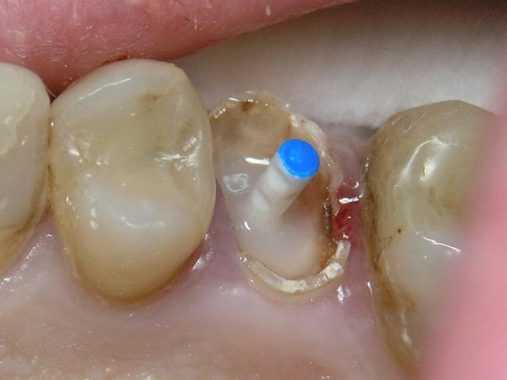

(Рис.3)

После изоляции по краям зуба устанавливается Core-форма. Мы используем ножницы для моделирования пришеечной части, чтобы улучшить прилегание формы к тканям зуба. Этот этап важен для создания внутреннего давления в композиционном материале.

(Рис.4)

Установка стекловолоконного штифта

Корневой канал обрабатывается адгезивом химического отверждения Luxabond (DMG). Затем наконечником для смешивания Colibri plus (Sulzer MIXPAC) вносится материал Luxacore Z (DMG).

После этого осуществляется установка стекловолоконного штифта Luxapost (DMG)

(Рис.5)